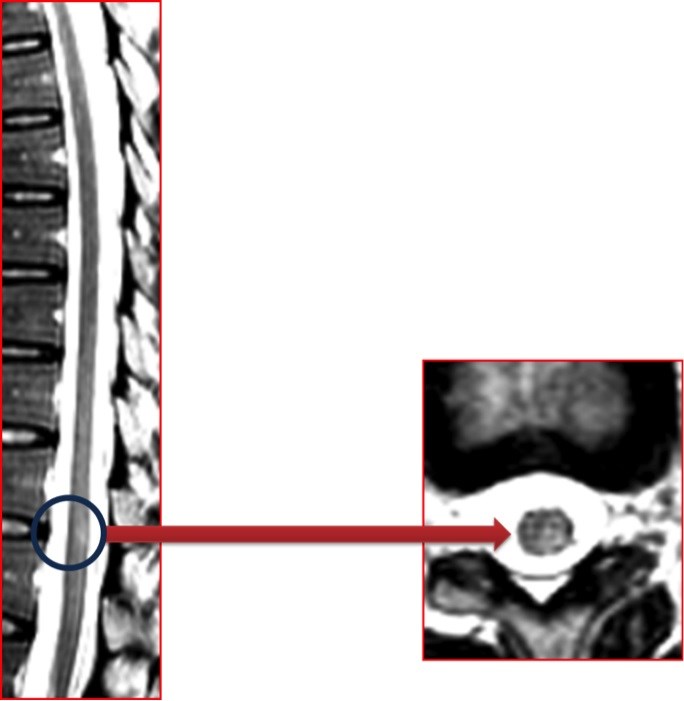

Spinal kord lezyonları

Spinal kord lezyonları, beyin MRG’sinde görülen lezyonların yaklaşık onda biri kadar sıklıkta olsa da, klinik açıdan son derece önemlidir. MS’li hastalarda spinal MRG incelemesi yapıldığında olguların yaklaşık %75’inde anormallik saptanır.

Kranial MRG’nin normal olduğu, ancak spinal MRG’de lezyon saptanan hastalarda MS tanısı daha dikkatle değerlendirilmelidir (bu oran %8–20 arasındadır). MS’i düşündüren spinal MRG özellikleri özetle şöyledir:

- Lezyon uzunluğu < 2 vertebra korpus segmenti,

- Sagital kesitte kord alanının %50’sinden küçük tutulum,

- Orta servikal ve torasik seviyelerde, periferal yerleşim,

- Asimetrik, multipl ve saçılmış lezyon dağılımı,

- Lateral / dorsal tutulumun anterior tutulumdan daha sık olması,

- Akut lezyonlarda ödem bulguları,

- Uzun dönemde fokal veya diffüz spinal kord atrofisi.

Bu özellikler, İMG – MRG-8 ve İMG – MRG-9 görsellerinde örneklenmiştir.

İMG – MRG-8: Spinal kord lezyonları.

İMG – MRG-9: Spinal kord lezyonları.